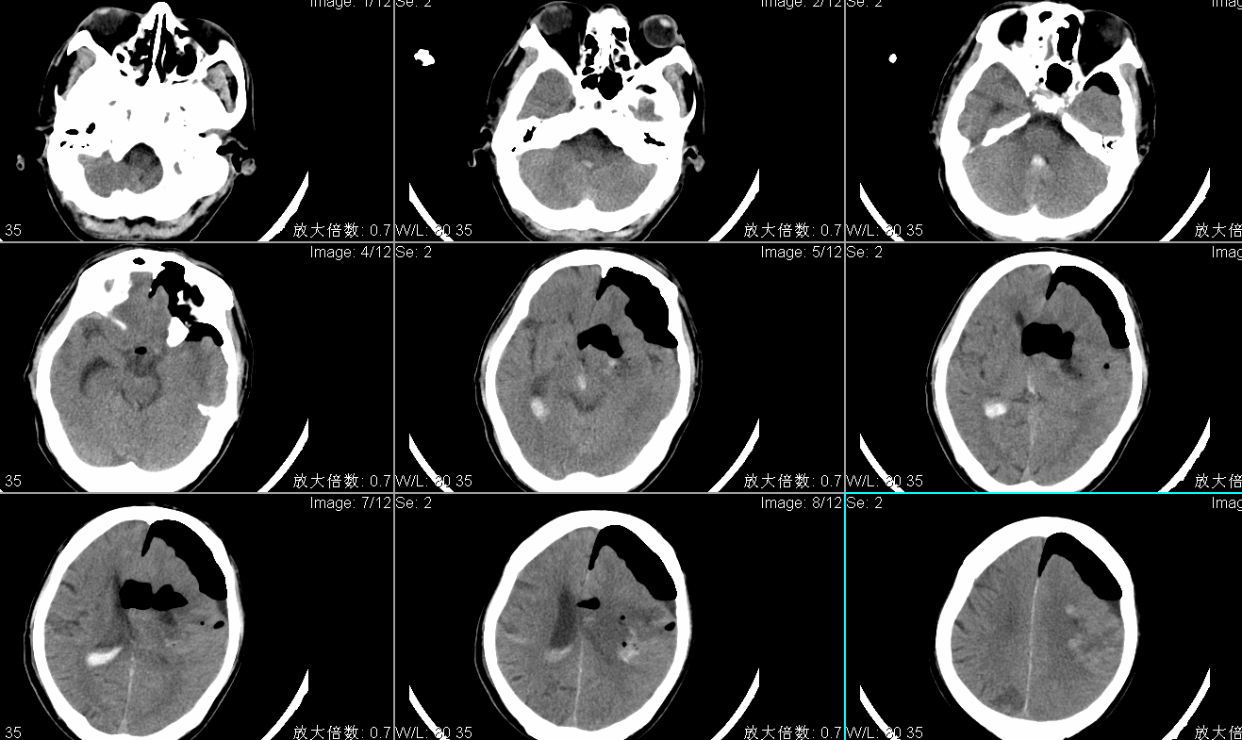

头CT显示左侧基底节区脑出血多田公式计算约100ml;